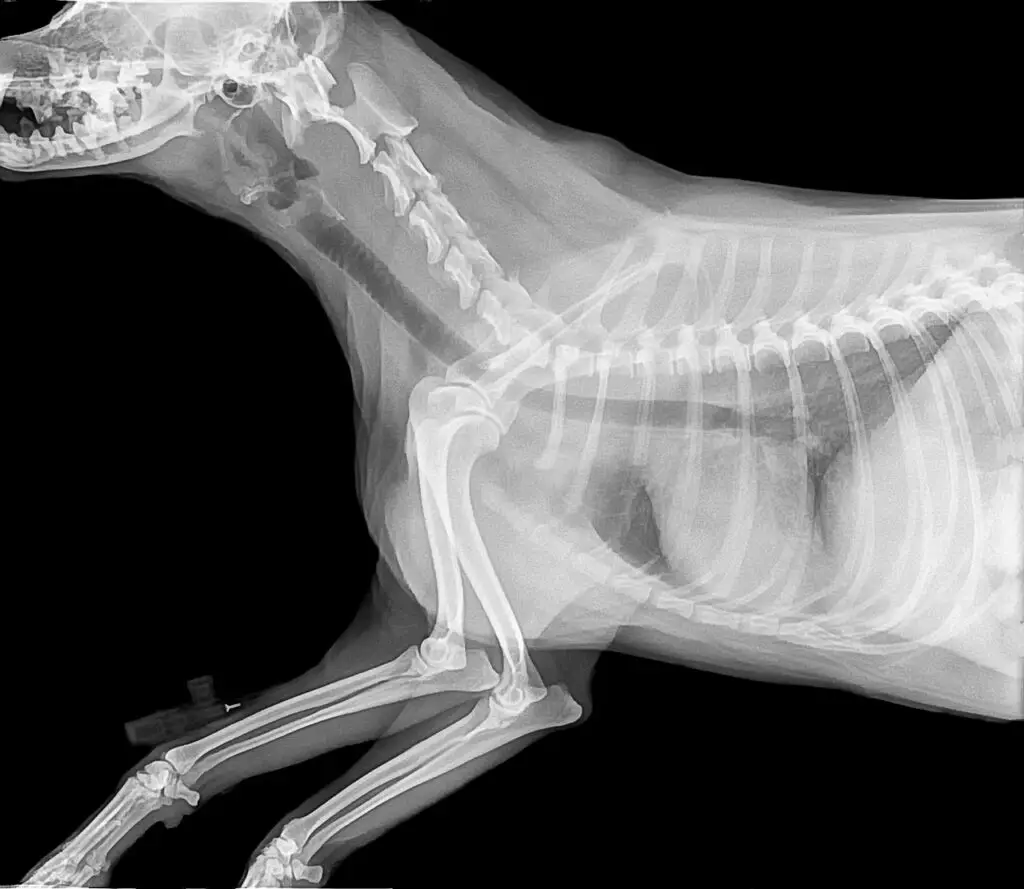

Dyrlægeundersøgelse

En grundig fysisk undersøgelse, røntgen, blodprøver eller scanninger kan være nødvendige for at finde årsagen.